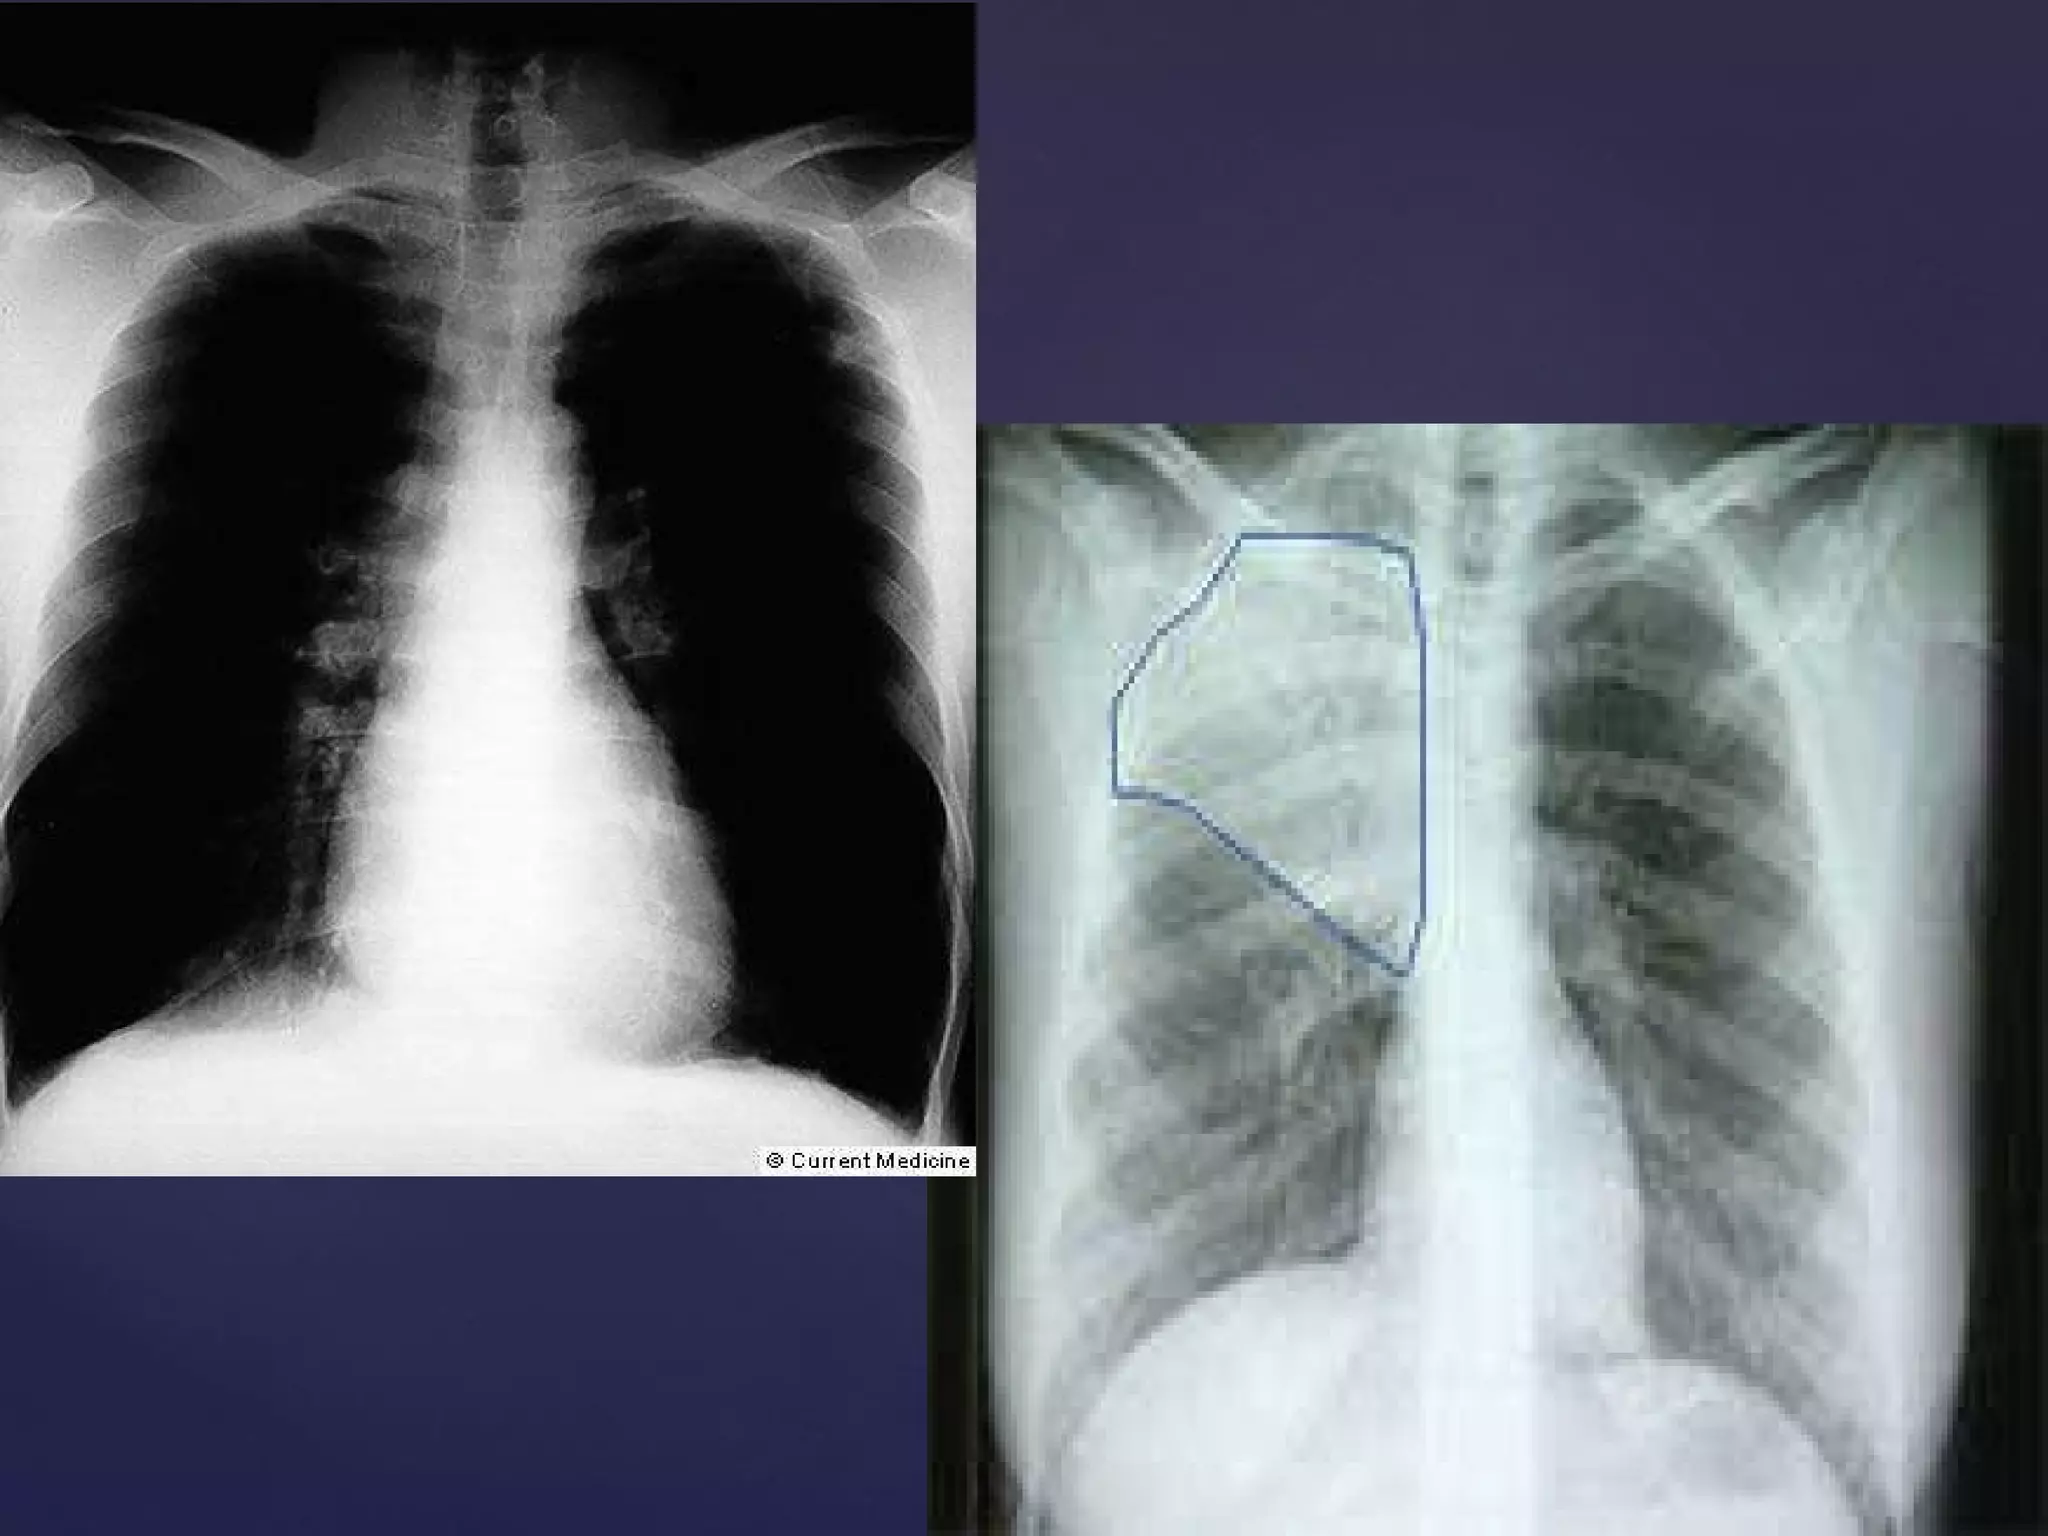

EXACERBACIÓN AGUDA DEL ASMA. CRISIS ASMÁTICA. CRISIS DE BRONCOESPASMO. SINDROME OBSTRUCTIVO BRONQUIAL. DESCOMPENSACIÓN ASMÁTICA. LEVE MODERADA AMBULATORIO - EMG CASI FATAL SEVERA Y STATUS EMG OBSERVACIÓN - UCI UCI

EXACERBACIÓN AGUDA DELASMA. CRISIS ASMÁTICA. CRISIS DE BRONCOESPASMO. SINDROME OBSTRUCTIVO BRONQUIAL. DESCOMPENSACIÓN ASMÁTICA. LEVE MODERADA AMBULATORIO - EMG CASI FATAL SEVERA Y STATUS EMG OBSERVACIÓN - UCI UCI